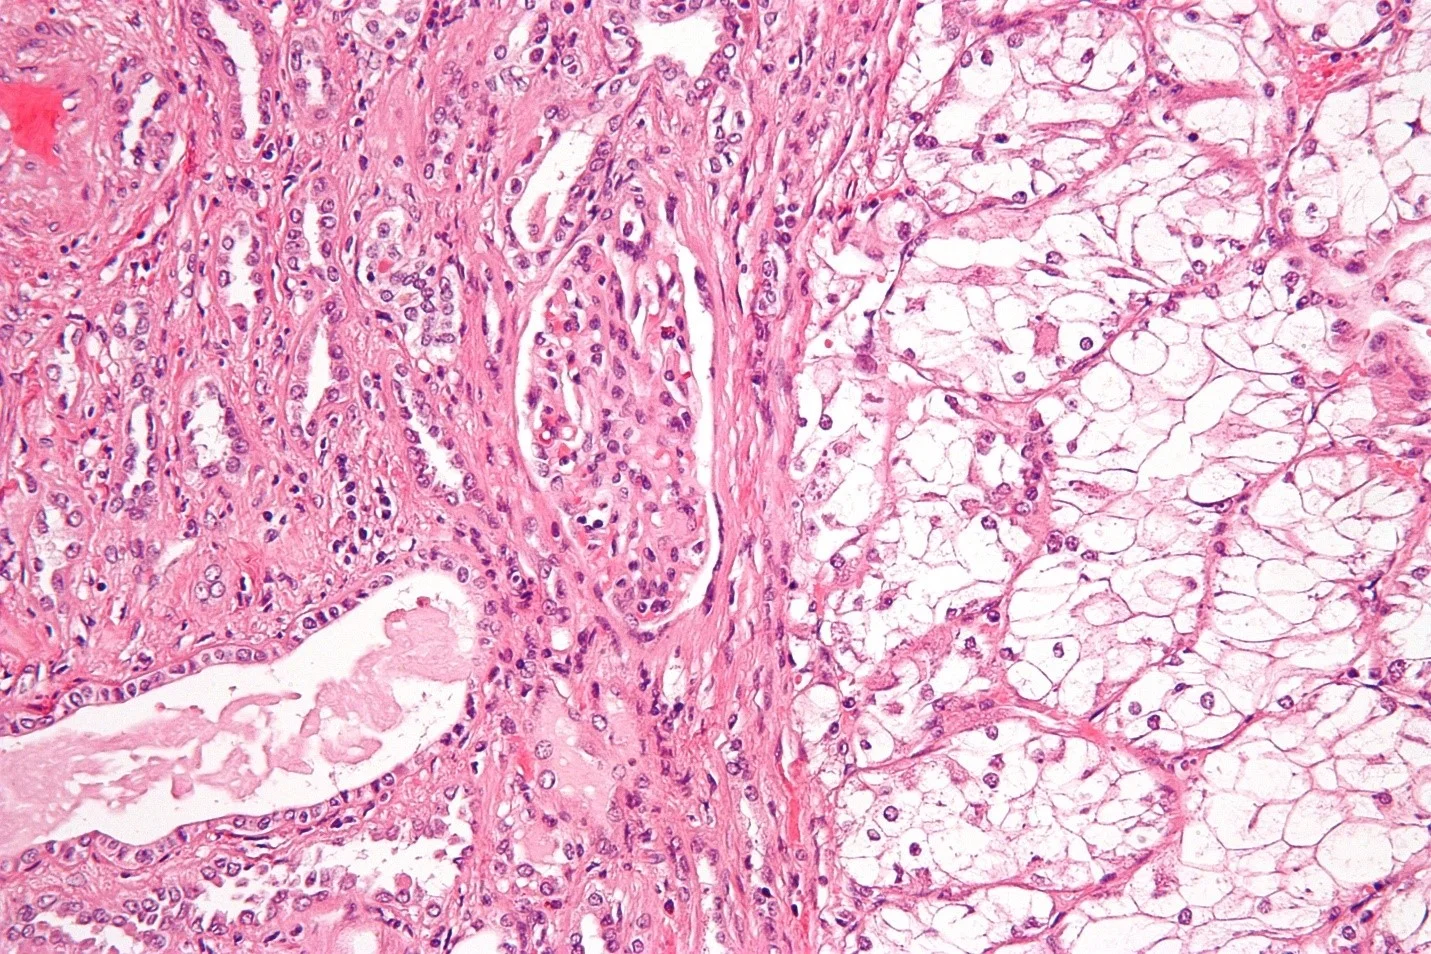

تومورهای ویلمز بر اساس نوع ظاهرشان در زیر میکروسکوپ (بافت شناسی آن‌ها) به 2 نوع عمده دسته بندی می‌شوند:

• بافت شناسی مطلوب (Favorable histology): سلول‌های سرطانی در این تومورها کاملاً طبیعی به نظر نمی‌رسند اما آناپلازی وجود ندارد (به پاراگراف بعدی مراجعه کنید). حدود 9 تومور از 10 تومور ویلمز بافت شناسی مطلوبی دارند. شانس درمان کودکان مبتلا به این تومورها بسیار خوب است.

• بافت شناسی آناپلاستیک (Anaplastic histology): در این تومورها، ظاهر سلول‌های سرطانی به طور گسترده ای متفاوت است و هسته سلول‌ها (قسمت‌های مرکزی حاوی DNA) بسیار بزرگ و مخدوش هستند. به این پدیده آناپلازی (anaplasia) می‌گویند. به طور کلی، درمان تومورهایی که در آن آناپلازی در سرتاسر تومور پخش می‌شود (معروف به آناپلازی منتشره یا diffuse anaplasia) نسبت به تومورهایی که آناپلازی فقط به قسمت‌های خاصی از تومور محدود می‌شود (معروف به آناپلازی کانونی یا focal anaplasia) سخت‌تر است.

بیوپسی/جراحی کلیه

در بیشتر مواقع، آزمایش‌های تصویر برداری می‌توانند اطلاعات کافی را در اختیار پزشکان قرار دهند تا تصمیم بگیرند که آیا کودک احتمالاً تومور ویلمز دارد یا خیر و بنابراین باید جراحی انجام شود یا خیر. اما تشخیص واقعی تومور ویلمز زمانی انجام می‌شود که یک قطعه کوچک از تومور برداشته شده و زیر میکروسکوپ بررسی شود. وقتی به سلول‌های تومورهای ویلمز نگاه می‌کنید، ظاهری متمایز دارند. پزشکان همچنین برای تعیین بافت شناسی تومور ویلمز (مطلوب یا آناپلاستیک)، نیز از این روش استفاده می‌کنند.

بافت شناسی تومور

عامل اصلی دیگر در تعیین پیش آگهی (وضعیت آتی) و درمان تومور ویلمز، بافت شناسی تومور است که بر اساس نوع ظاهر سلول‌های تومور در زیر میکروسکوپ است. بافت شناسی می‌تواند مطلوب یا آناپلاستیک باشد. این موارد با جزئیات بیشتر در مبحث تومورهای ویلمز چیست؟ توضیح داده شده است.